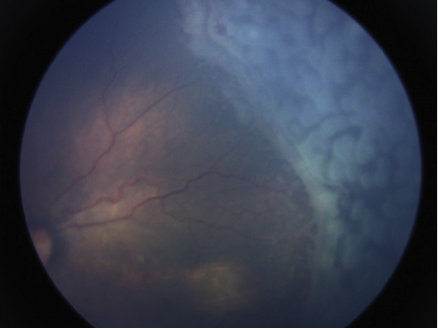

Zone III, stage 3 with plus disease is not recognised as an indication for treatment in either study, although these babies are sometimes treated. In addition another indication for treatment called Aggressive Posterior ROP (APROP) is increasingly being recognised. This condition is characterised by dilated and tortuous vessels in the posterior pole, although clear definitions and treatment indications are lacking.

Laser treatment

Laser therapy is applied to the region of avascular retina that is anterior to the ridge or demarcation line. Both diode and green (argon or double frequency Neodymium: Yttrium Aluminium Garnet) can be used and delivered via a laser indirect ophthalmoscope. General anaesthesia is ideal for the procedure although sedation and/or topical anaesthesia is used extensively in the South Asian region. The baby has to be monitored during the procedure.